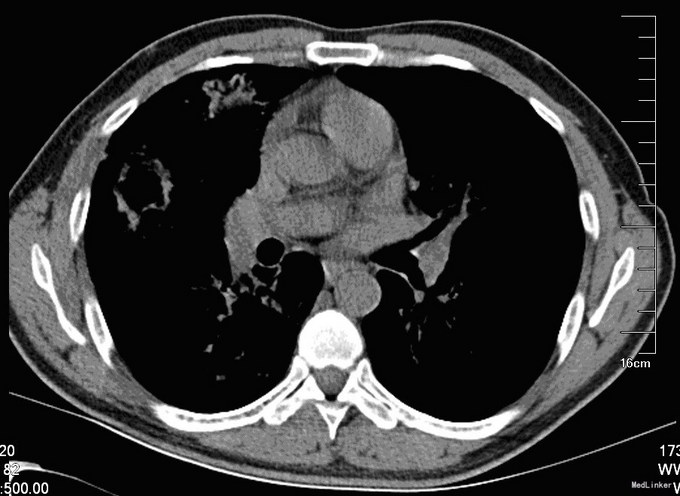

入院后,化验:血常规:白细胞:15600/mm3,嗜酸性粒细胞分数:20.3%; ESR 69 mm, CRP 176 mg/l,风湿因子:656 UI/ml,pANCA antibodies 阳性. 行肺CT:见双肺多发呈类圆形内部稍低密度影,大小不一,较大者约3.2*2.6cm(图1)。考虑肺泡出血和嗜酸性粒细胞侵润。鼻黏膜活检病理证明大量嗜酸性粒细胞侵润。根据上述,诊断为嗜酸性肉芽肿性多血管炎(EGPA,eosinphilic granulomatosis with polyangiitis)。予激素和免疫抑制剂等对症治疗。患者激素减量过程中出现咳血反复,周身及肛周出现溃疡破溃,再次与甲强龙500mg冲击后症状缓解,口腔及肛周、下肢溃烂均较前好转。进食软食一天后突然出现腹痛、发热,腹膜炎症状,查体:全腹压痛,以下腹部为重,伴有反跳痛及肌紧张。完善全腹CT检查考虑消化道穿孔(图2),EGPA并发穿孔的患者行剖腹探查,小肠穿孔修补术。术中见:腹腔小肠肠管明显扩张,多处脓苔,广泛粘连,腹腔内黄绿色渗出100ml,吸尽渗出探查,见距回盲部5cm至距TREITZ韧带150cm之间小肠多发穿孔共11处,较大者破孔3cm*3cm(图3),较小者0.4*0.4cm,予以4-0可吸收线沿肠壁横轴缝合肠壁全层及浆肌层。病理(图4):(小肠穿孔周缘)炎性肉芽组织。术后予以禁食水抗炎补液抑酸及激素治疗。术后6天因血管炎病情反复发作,出现发热,皮肤红斑,7天出现肠瘘,予以双腔套管持续冲洗接负压吸引后逐步愈合后出院。继续风湿免疫科随诊治疗。未有再次发生消化道穿孔。